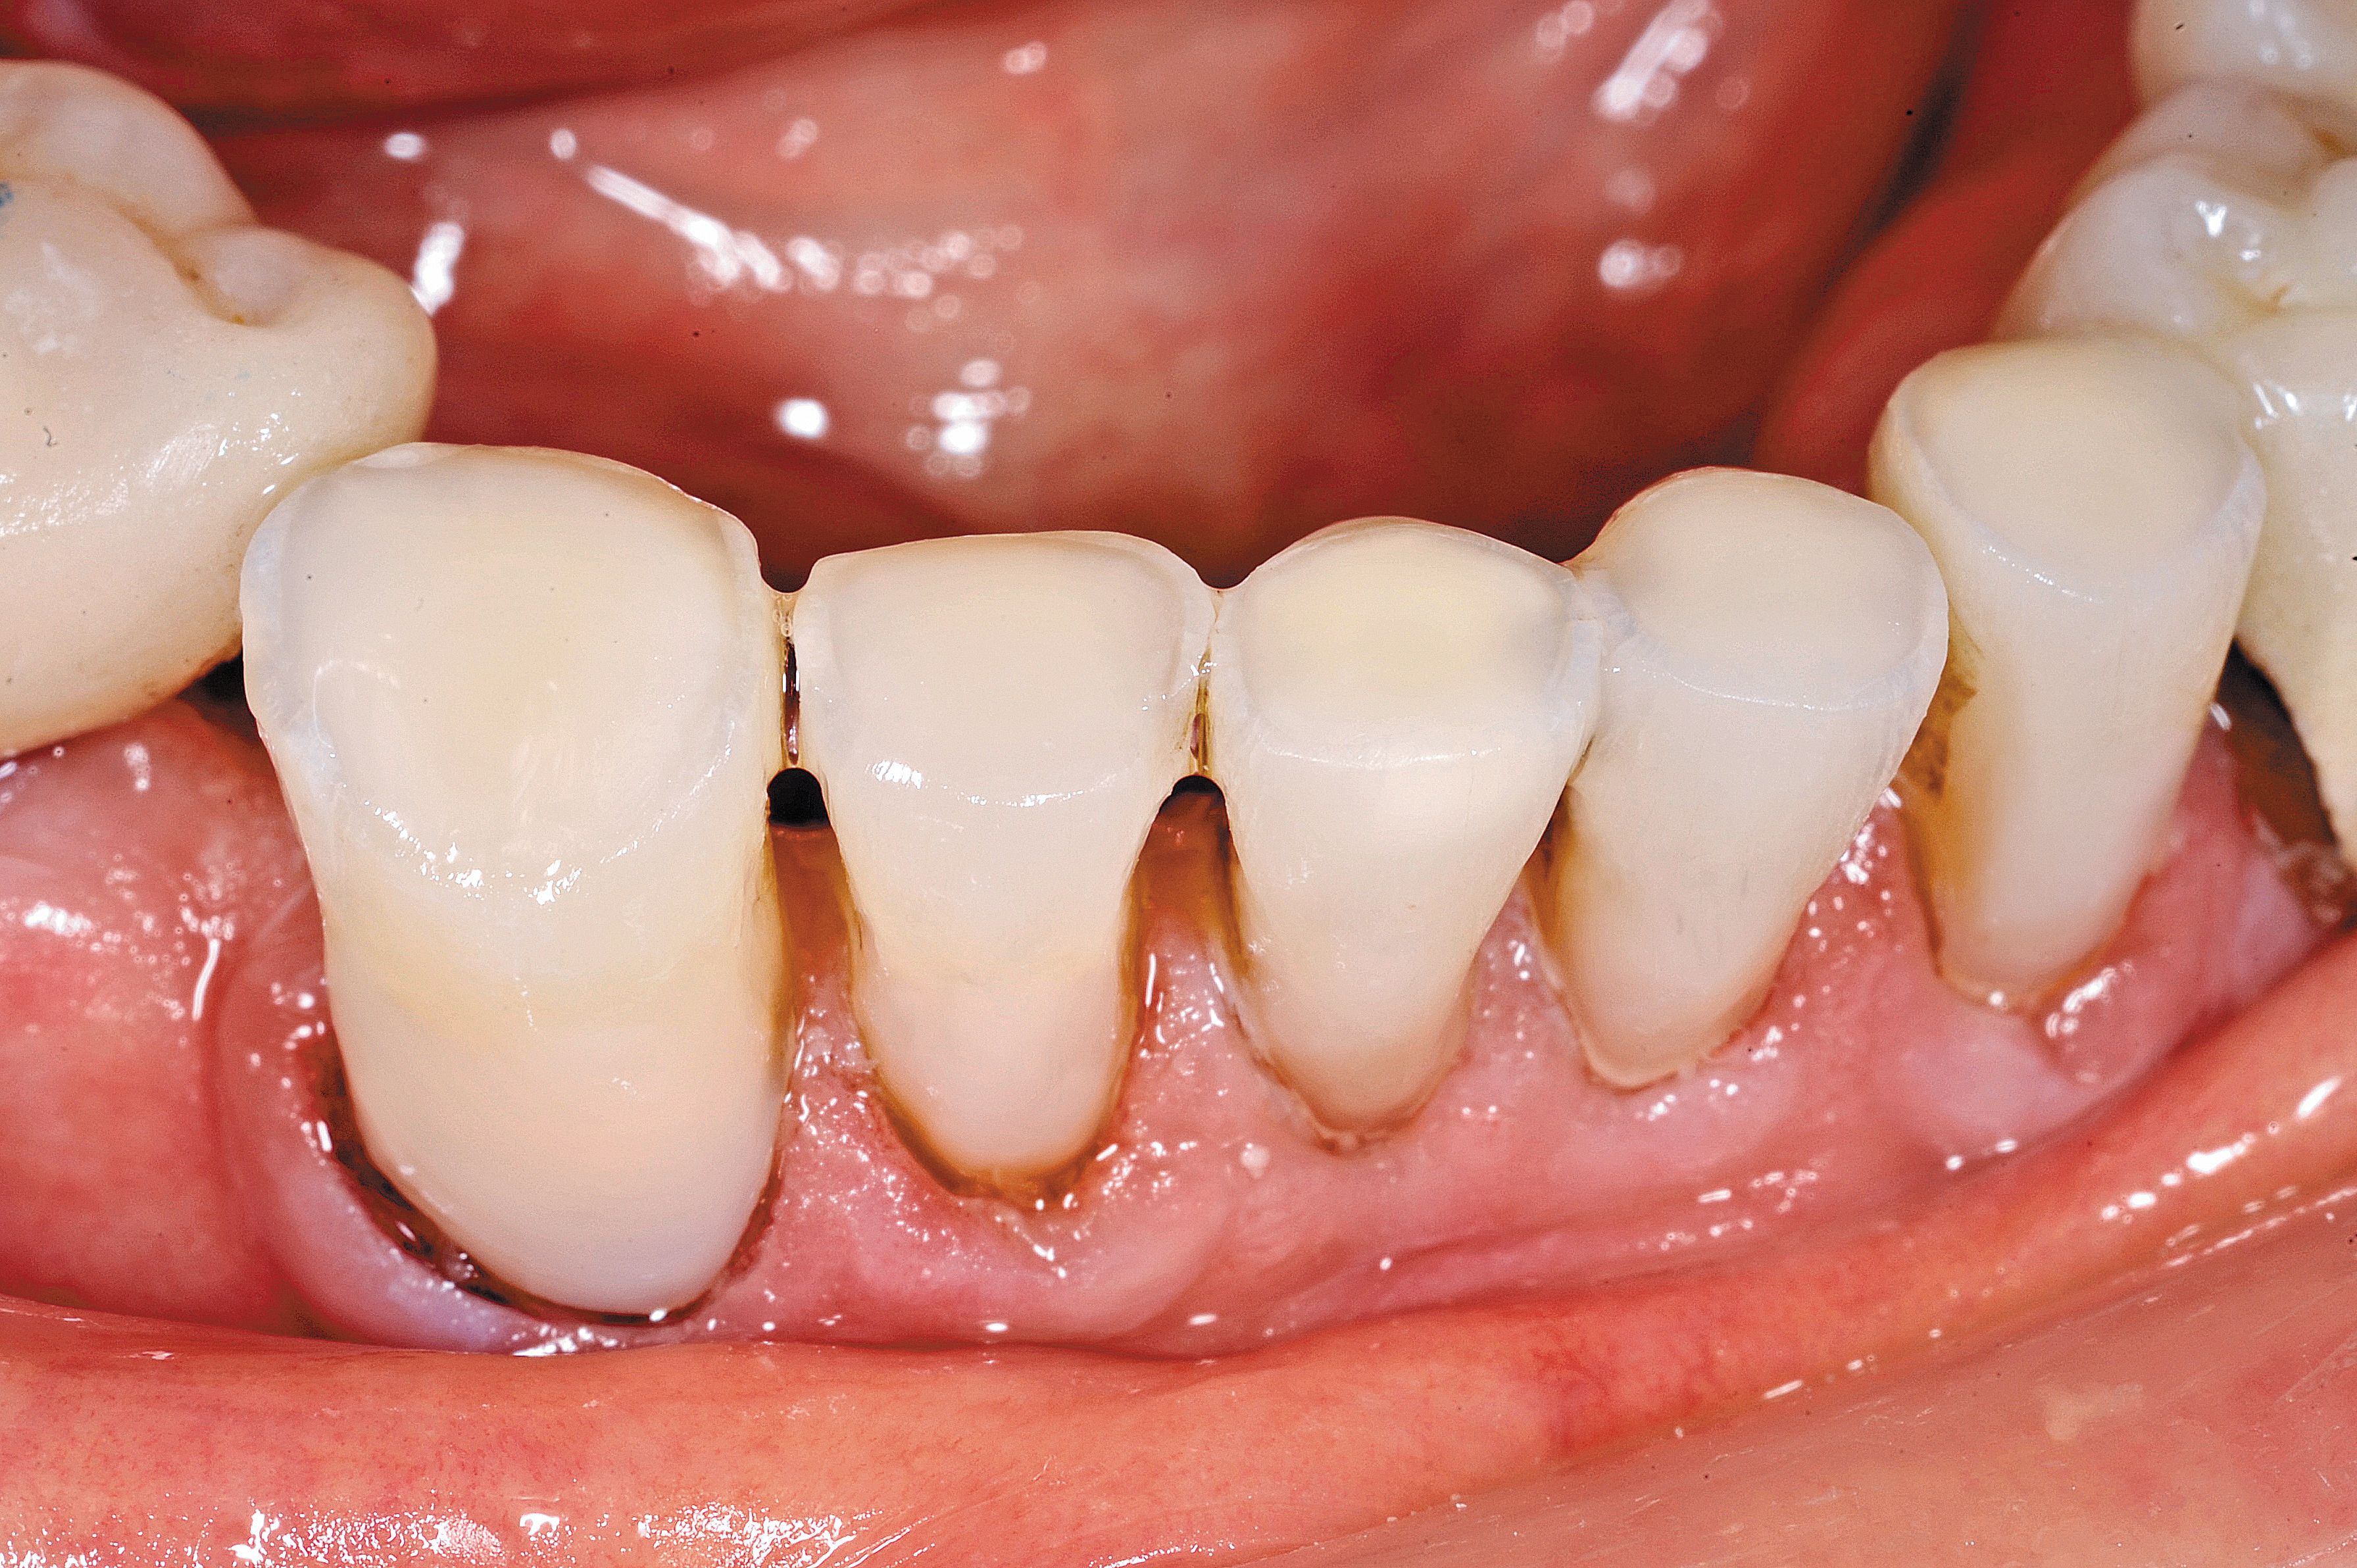

Fig. 2

The wear of the opposing denture and acrylic teeth was significant enough to see the secondary dentin of the pulp.